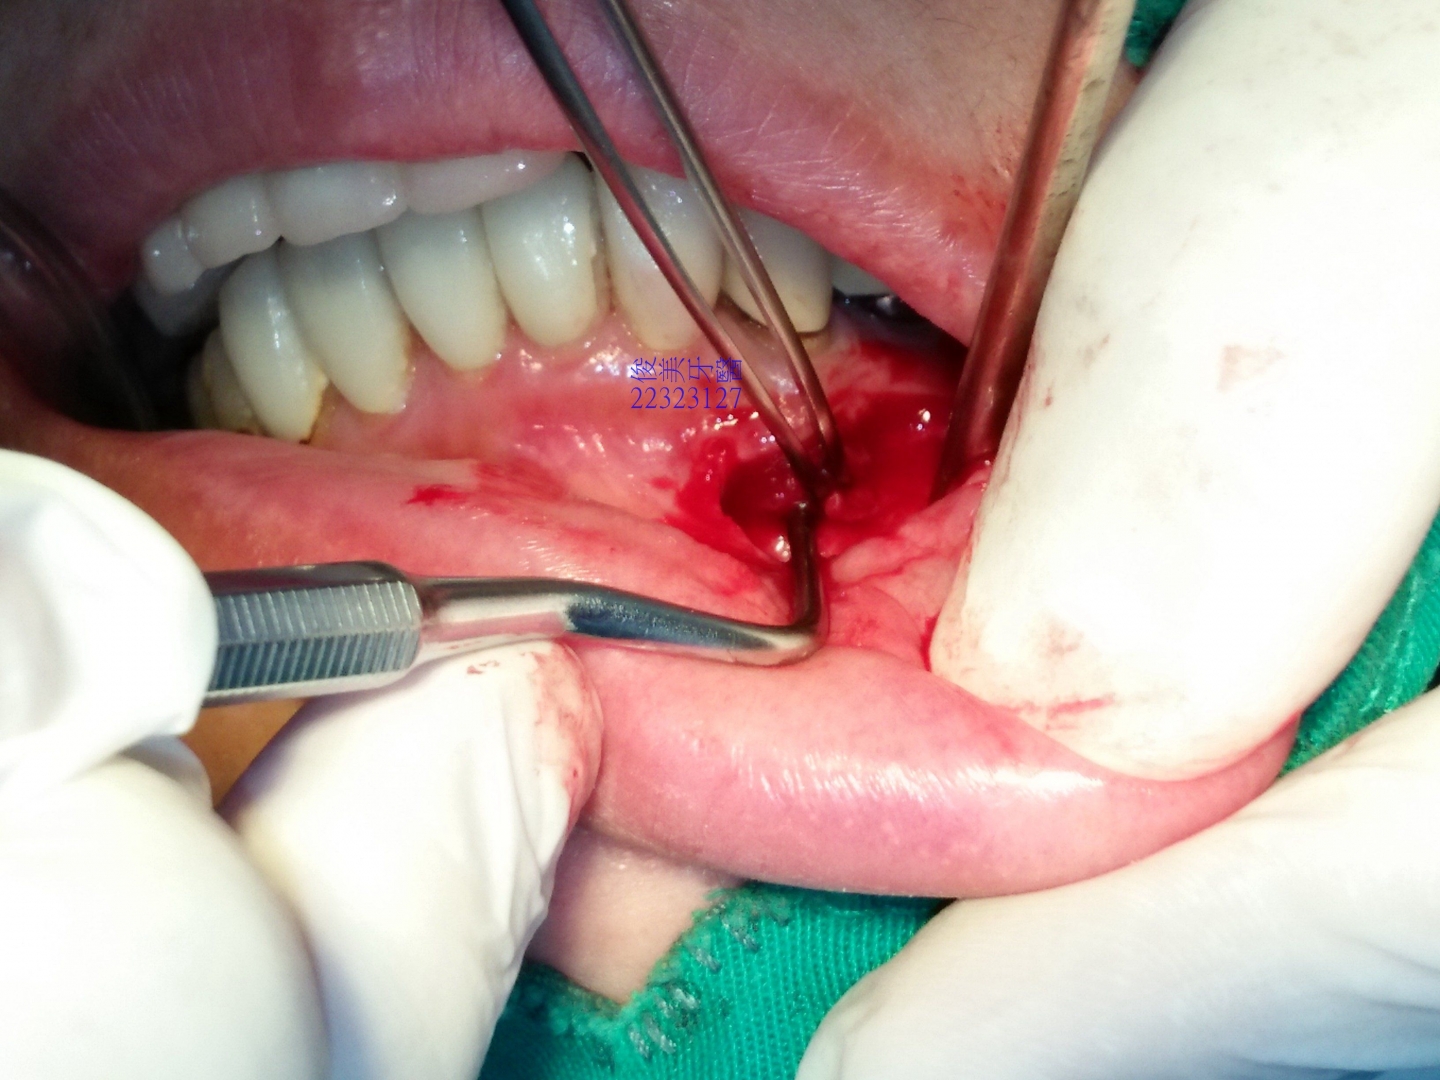

一翻開牙齦就發現不正常組織已穿透骨頭。

牙根已裸露無骨頭保護。

將異常生長組織刮除乾淨.....